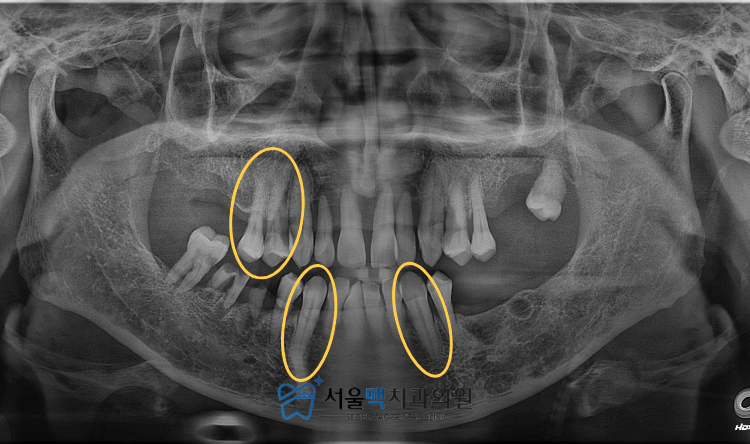

보존적인 치료를 통해

치아를 살려보고자 노력하는 것이

치과의사로서의 본분이지만

이번에 가양역치과 내원하신 환자분의 경우

남아있는 치아들을 유지하는 것이

오히려 잇몸뼈의 추가적인 파괴를 유발하고

향후 임플란트 식립을 위한

토대마저 무너뜨릴 위험이 컸습니다.

이에 환자분과 충분한 상담을 거쳐

현재 기능을 상실한 대다수의 치아를 발치하고

임플란트를 통해 전체적인 구강 기능을

재건하기로 결정하였습니다.

제 기능을 수행하지 못하고

염증의 원인이 되고 있는 치아들을

조심스럽게 발치하는 과정부터 치료를 시작했습니다.

결과적으로 오른쪽 위 작은어금니 2개,

아래의 송곳니 양쪽 2개를 제외한

모든 치아를 발치하였으며,

이후 치주염으로 인해 약해진 잇몸을 회복하고,

임플란트를 식립할 부위의

건강 상태를 회복하는 데 주력하였습니다.